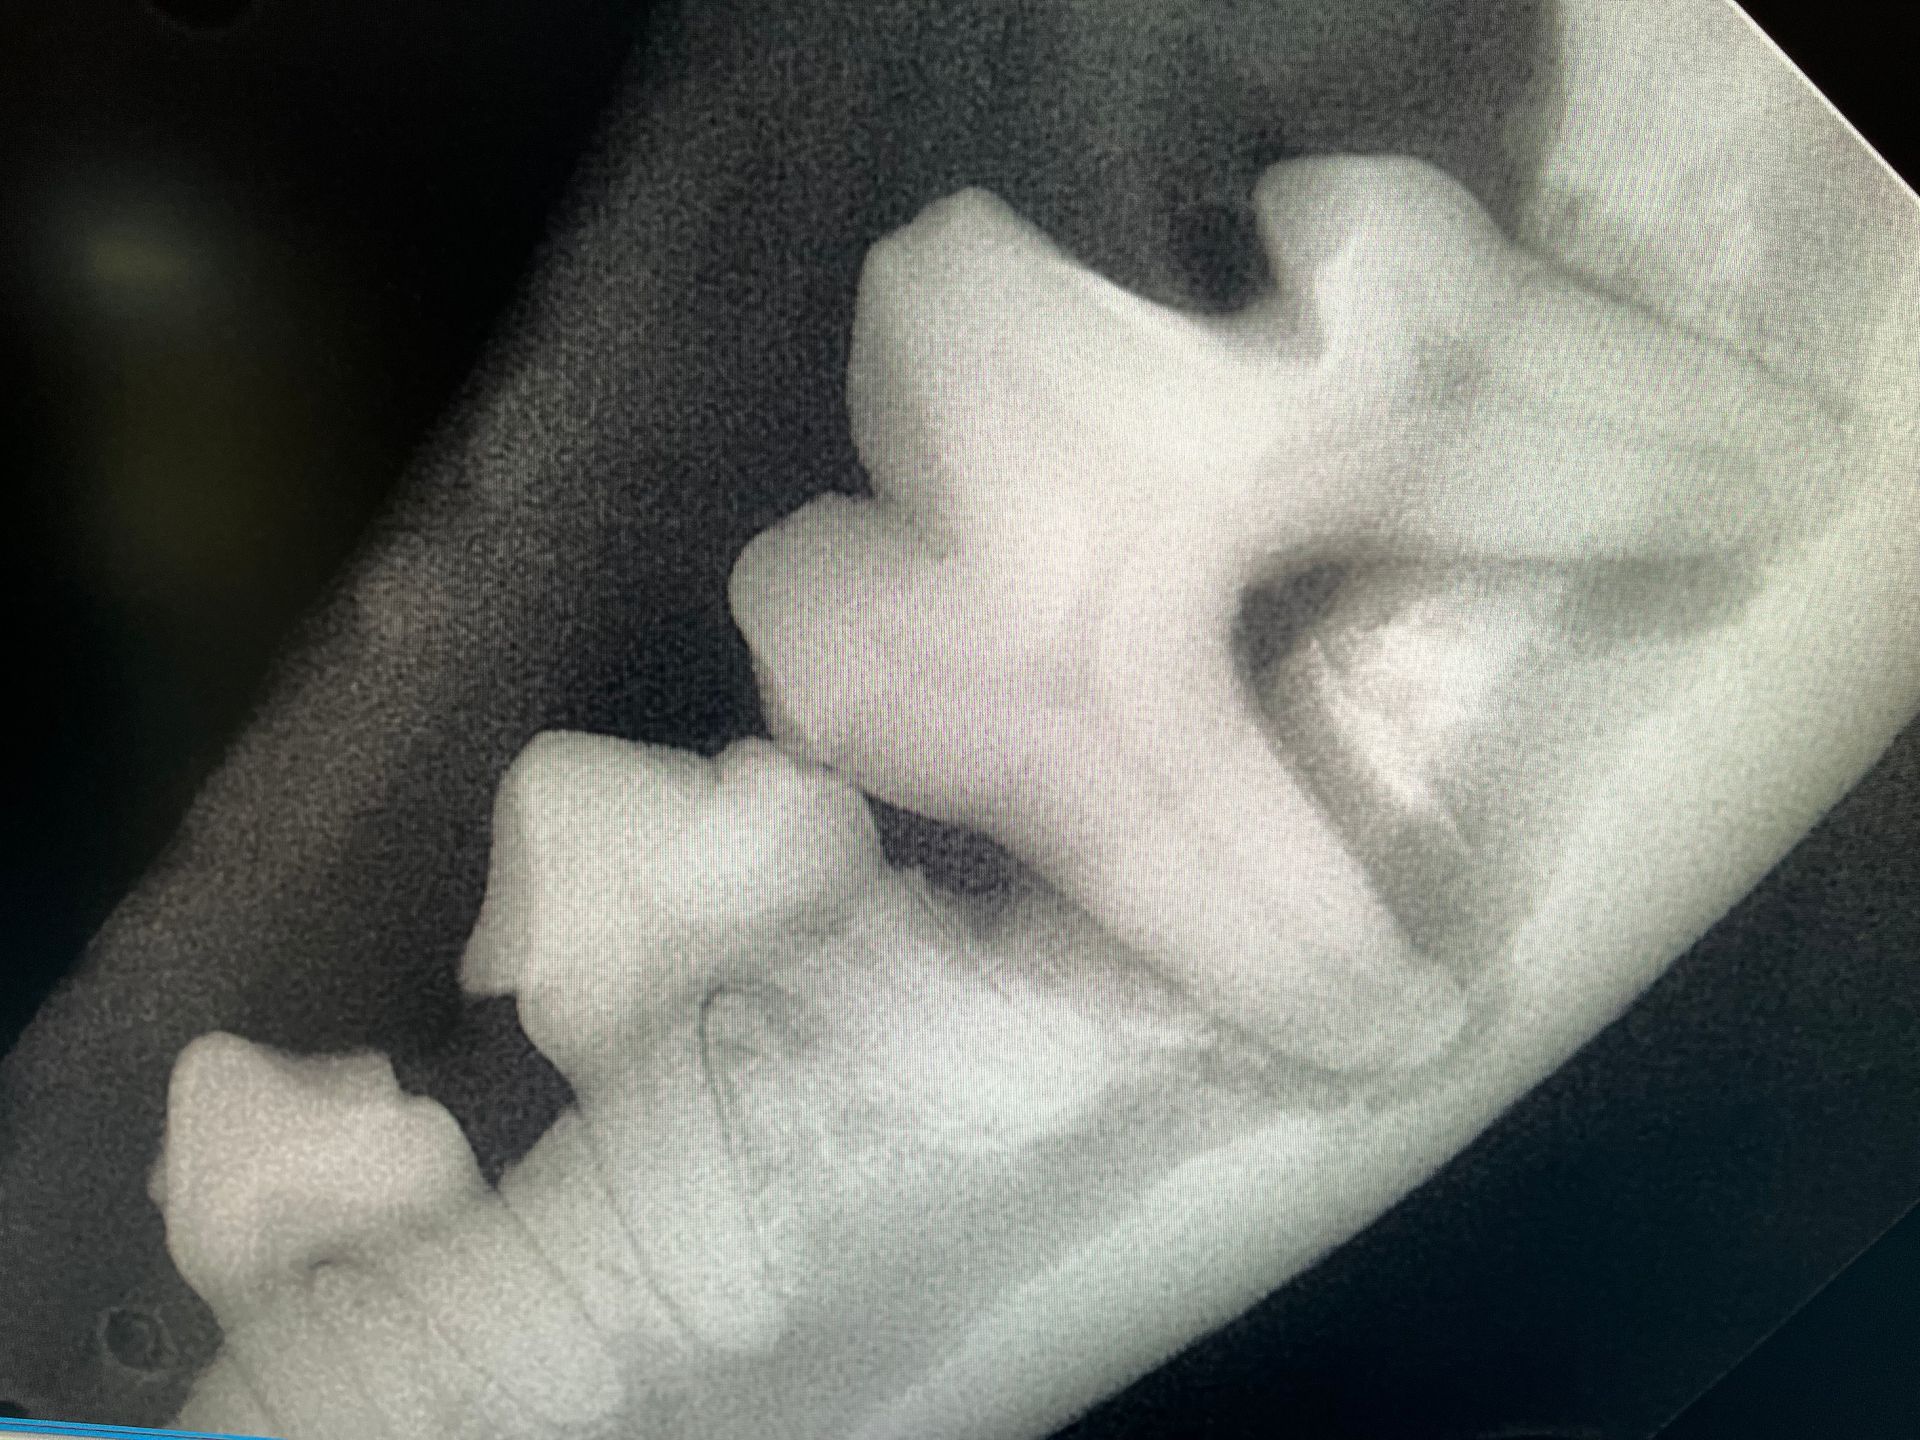

Dental Care

We help prevent and treat dental disease — because your dog’s oral health is vital to their overall

wellness. We firmly believe in anesthetic dental cleaning and intra oral radiographs for all out patient. Radiographs give us a look below the gums where we often find disease that is not otherwise visible.